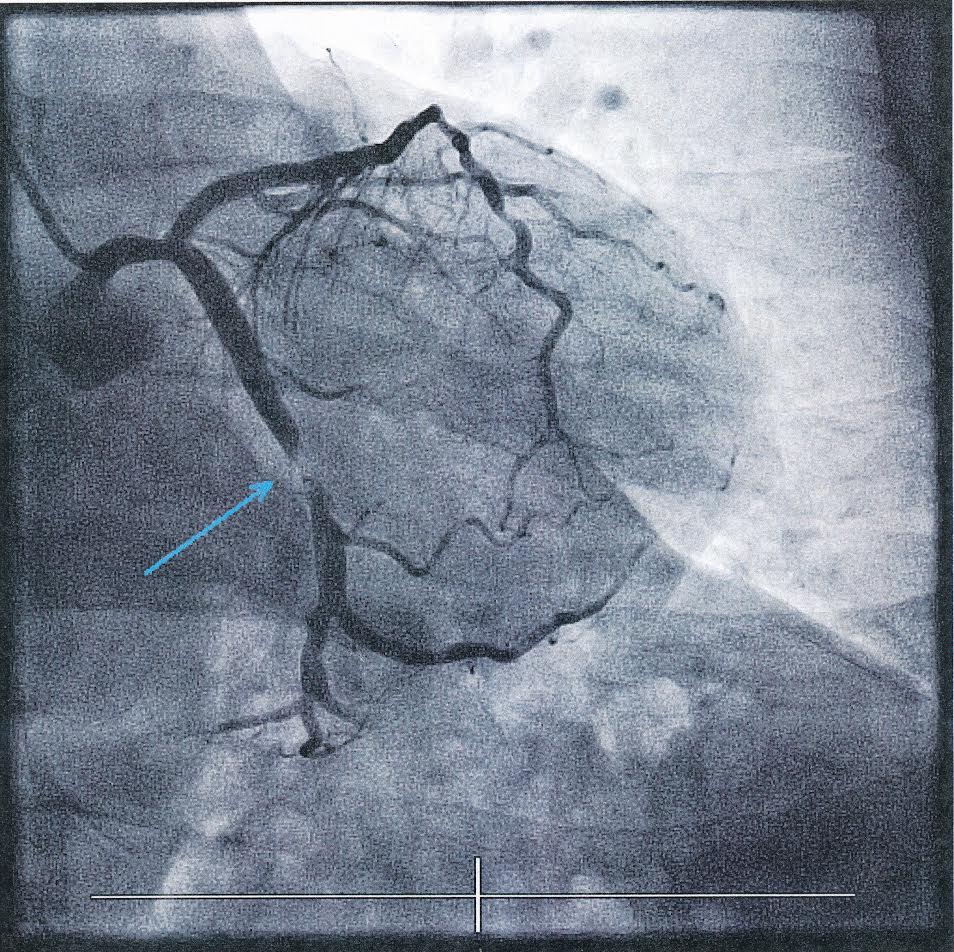

Kính chia sẻ 2 hình chụp tim của Thông Đạo. Hình mạch máu bị gián đoạn là trước khi thông tim. Hình mạch máu thông suốt là sau khi chữa trị (procedure) trong 1 giờ. Thành tâm niệm ân Y học Hiện đại!

Ngày 29/5/2019 vào bệnh viện Kaiser soi tim, một mạch máu khác bị nghẽn đến 99%, thế là thêm một stent nữa được đặt vào mạch máu để thông tim. Nguyên nhân nghẽn tim lần nầy rất rõ ràng: do thức ăn nhiều dầu, muối và đường. Đường trong máu tăng cao, A1C trung bình 3 tháng lên đến 8. Lại phải kiên trì thực tập từng bước như lần đầu một lần nữa.

Bác sĩ cho biết, hai stents như cái lưới, đã được gắn vào đầu một sợi giây, chuyền qua mạch máu dưới háng bên phải, từ từ đưa dần lên cao, rồi đặt vào mạch máu bị nghẽn trong trái tim nhỏ bé của mình. Nhờ vậy mà dòng máu đã được thông suốt. Thật mầu nhiệm như chuyện cổ tích! Thì ra, đau thốn ở háng là bác sĩ rút kim chuyền stents ra, và thuốc mê vừa hết hiệu lực.